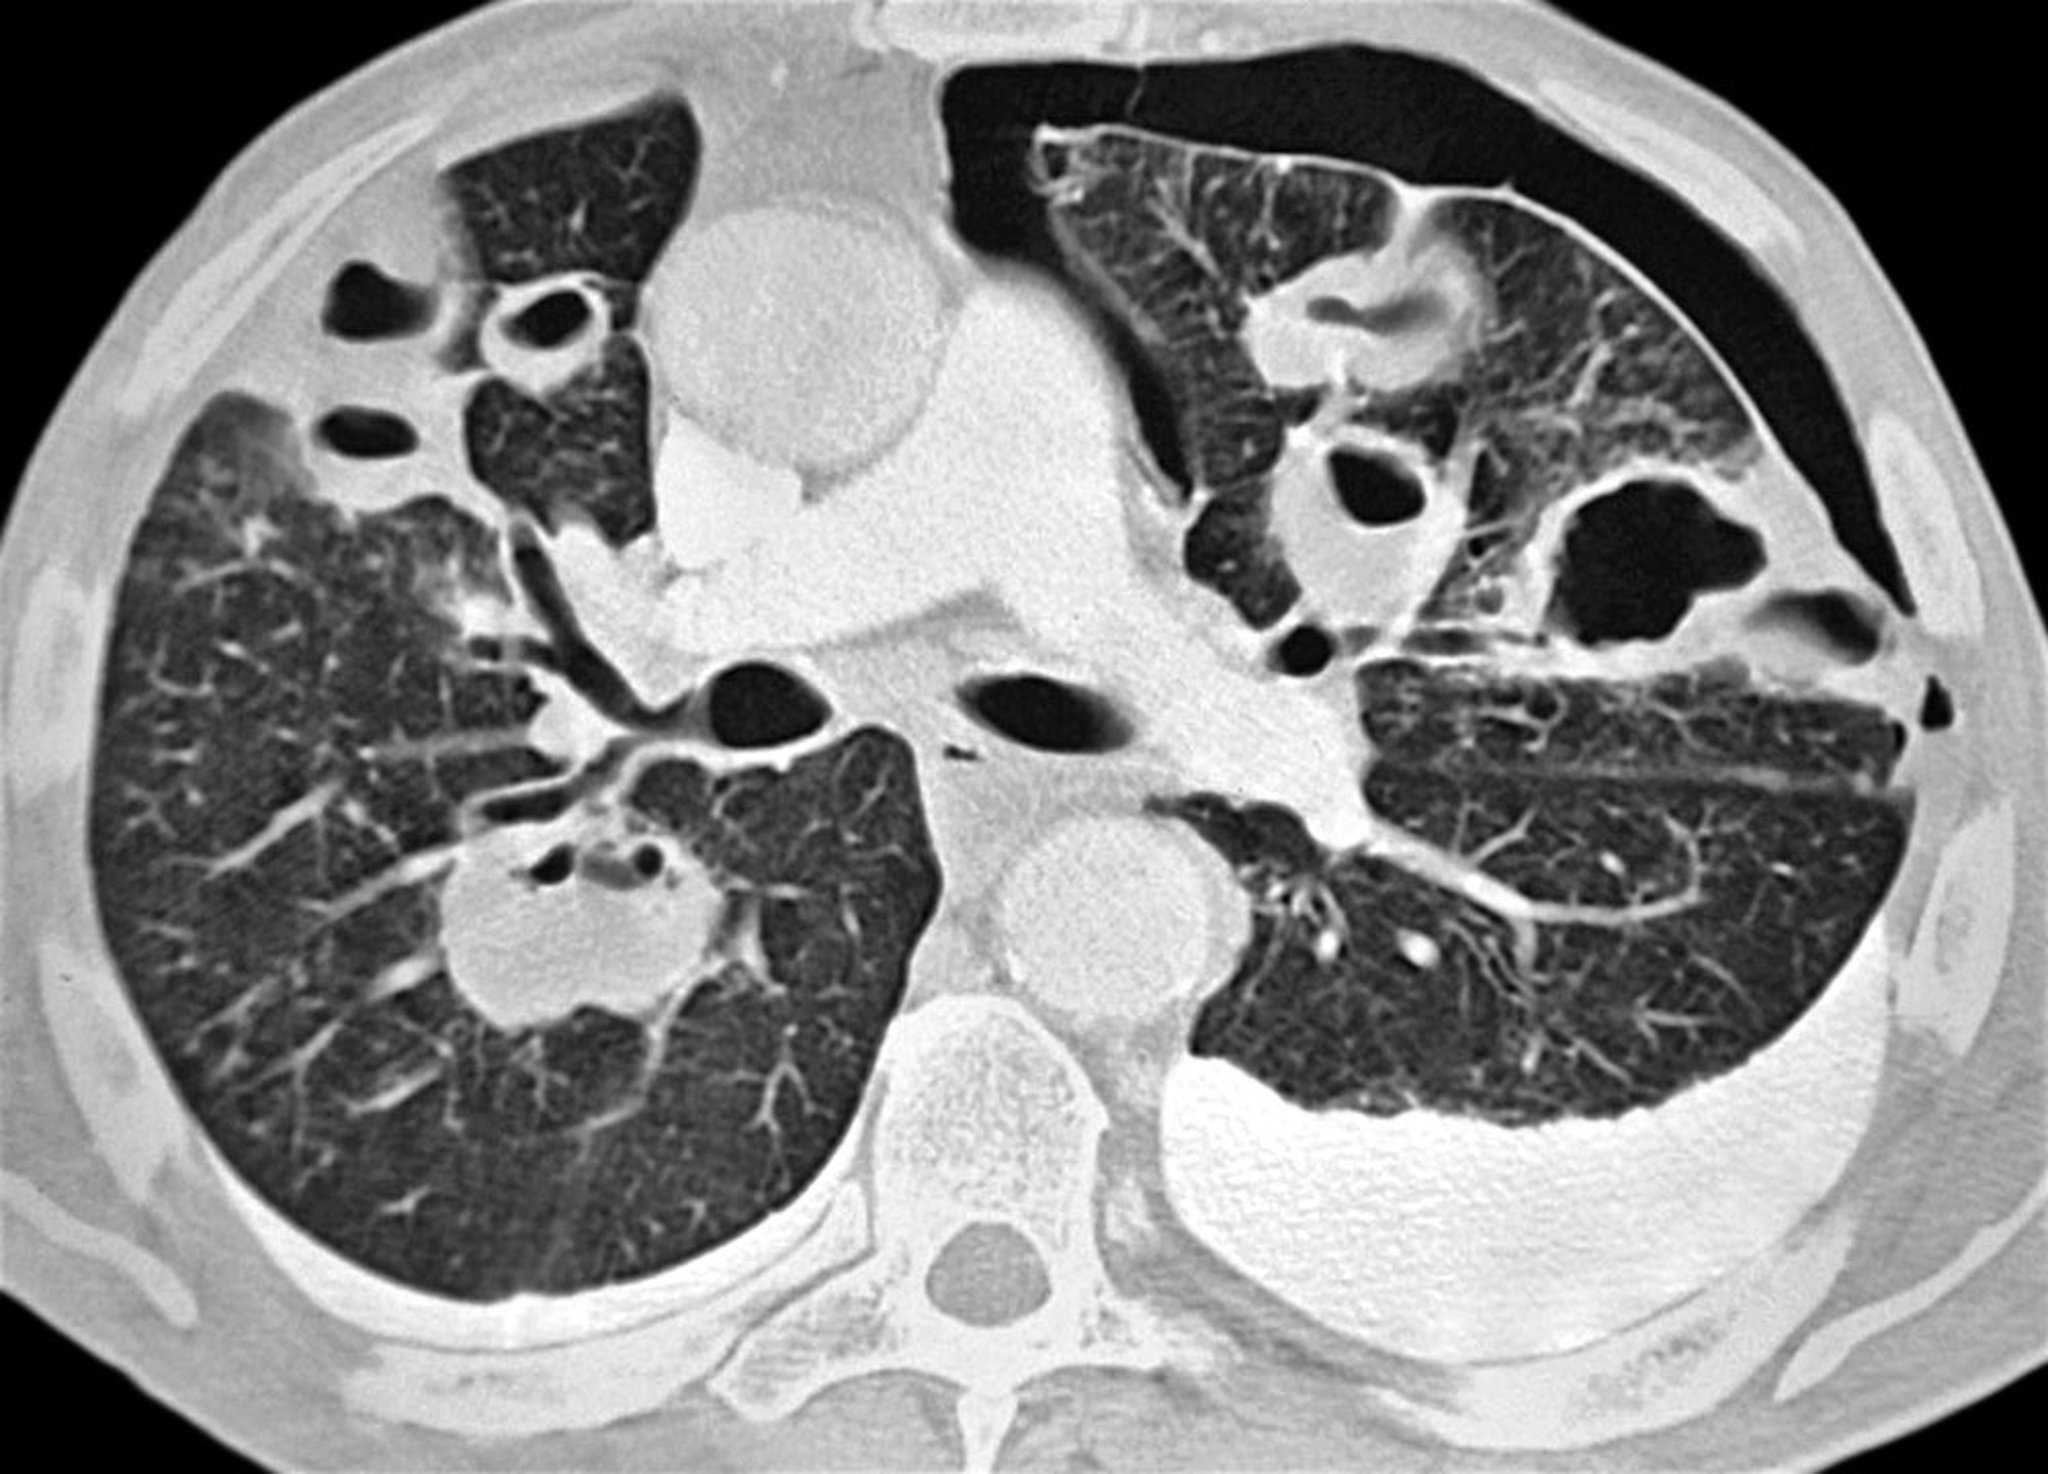

La TC también permite una excelente visualización de los neumotórax y la enfermedad relacionada en pacientes en decúbito supino.